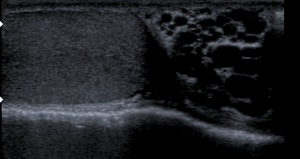

| مقطع عرضي يوضح الإصابة بدوالي الخصية. | |

- إذا لم يتم التوصل لنتيجة بالفحص السريري يتم عمل سونار للخصية.